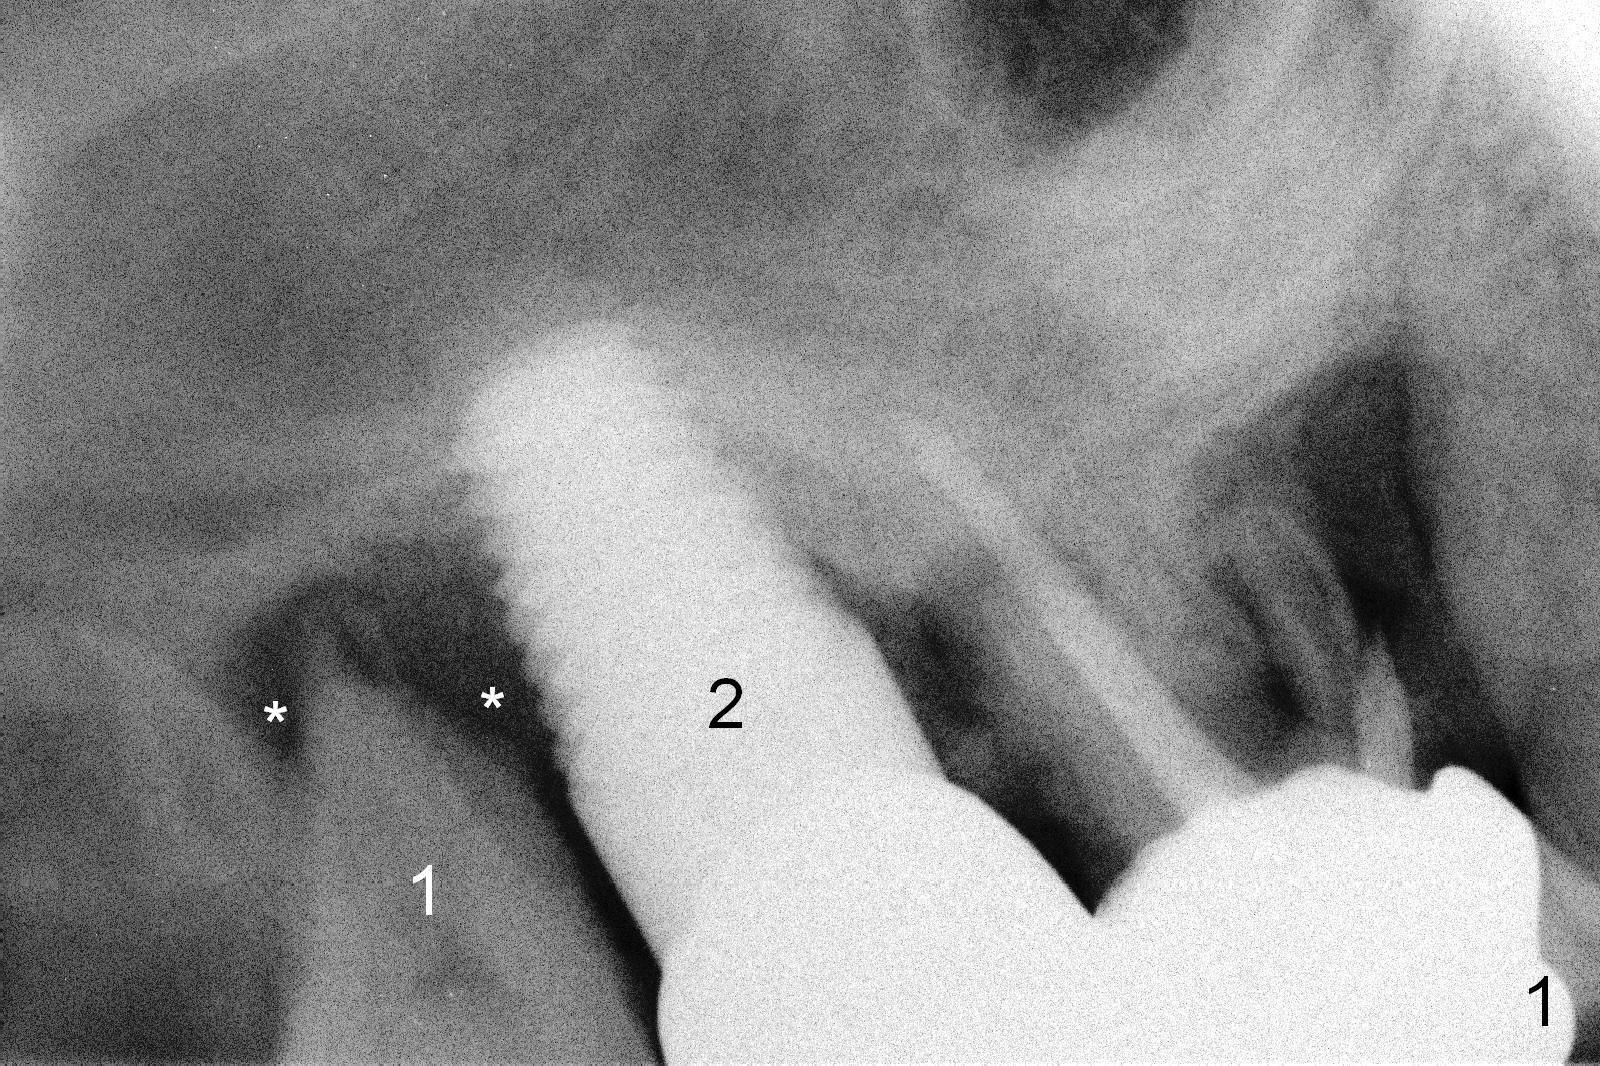

A 62-year-old man (CJ) had food impaction between the tooth #1 and the implant at #2 six months post cementation of the crown at #2. At the most recent visit (1.5 years post cementation), symptoms and signs of infection around the tooth #1 appear to get worse (Fig.1 *). The patient accepted treatment plan (#1 extraction and immediate implant, Fig.2).

After extraction, the socket is curetted thoroughly, the implant threads cleaned with Titanium brush, and the wound treated with Metronidazole. It appears that a 4.5x10 mm bone-level implant is appropriate for the site (Fig.2).